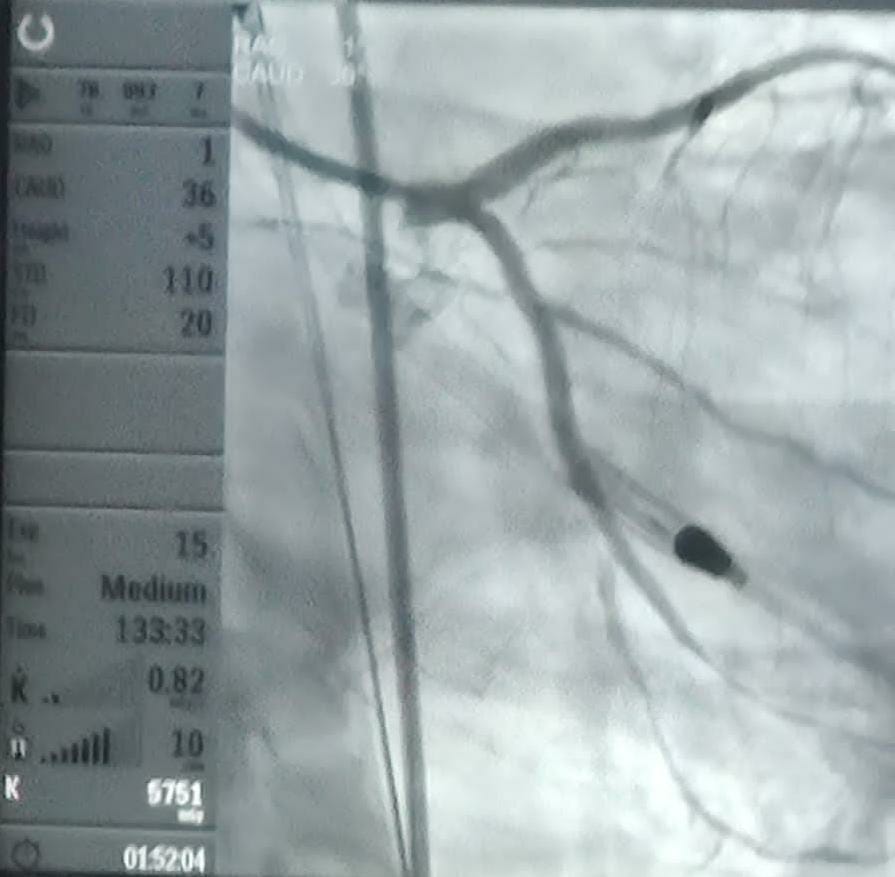

నమస్తే శేరిలింగంపల్లి: యూఏఈలో పనిచేస్తున్న ఓ 49 సంవత్సరాల వ్యక్తికి 2002లో కిడ్నీ మార్పిడి జరిగింది. అయితే 2018లో కిడ్నీ మార్పిడి ఫెయిల్ అయినట్లు నిర్ధారణ జరిగింది. దాంతో పాటు హార్ట్ పంపింగ్ కూడా ఫెయిల్ అయినట్లు కరోనరీ ఆంజియోగ్రామ్ ద్వారా తెలిసింది. రెండు నాళాల్లో పూర్తి బ్లాకేజీలతో ట్రిపుల్ వెజిల్ డిసీజ్ నిర్ధారణ అయింది. యూఏఈలో హార్ట్ ఫెయిల్యూర్ స్టెబిలైజేషన్ గురించి ఎన్నోసార్లు హాస్పిటల్లో అడ్మిట్ అయ్యాడు. అయినా ఆయన కండీషన్ కఠినంగా ఉండటంవల్ల ఇంటర్వెన్షన్ చేయలేకపోయారు. అలాగే ఈ సివియర్ హార్ట్ ఫెయిల్యూర్ కండిషన్ కారణంగా రెండోసారి కిడ్నీ మార్పిడికి కూడా ప్లాన్ చేసుకోలేకపోయాడు. ఇతరుల ద్వార సమాచారం అందుకున్న కుటుంబ సభ్యులు ఇటీవల ఆయనను మెడికవర్ హాస్పిటల్లో కార్డియాక్ కన్సల్టేషన్ కోసం డాక్టర్ శరత్ రెడ్డిని సంప్రదించారు. ఆయనతో పాటు నెఫ్రాలజిస్ట్ కమల్ కిరణ్లు రోగి క్లినికల్ సమాచారాన్ని పూర్తిగా తెలుసుకున్నారు. ఆపైన పెర్క్యూటేనియస్ ఎల్వీ అసిస్ట్ డివైజ్ ‘ఇంపెల్లా’ సాయంతో ఆ పేషెంట్ హార్ట్ బ్లడ్ వెజిల్ బ్యాకేజీలను పెర్క్యూటేనిషస్ ఇంటర్వెన్షన్ పద్ధతి ద్వారా తొలగించారు. ఐదు గంటలపాటు సాగిన ఈ ఆపరేషన్ పూర్తి విజయవంతమయ్యి రోగి ప్రాణపాయం నుంచి బయటపడ్డారు. కేవలం ఒకటిన్నర రోజు వైద్యుల పర్యవేక్షణలో ఉంచి అవసరమైన మెడికేషన్ ఇచ్చి డిస్చార్జి చేశారు.

మేడికవర్ హాస్పిటల్ డైరెక్టర్, ఇంటర్వెన్షనల్ కార్డియాలజిస్ట్ డాక్టర్ శరత్ రెడ్డి మాట్లాడుతూ.. ‘‘ఇంపెల్లా అనేది యూఎస్ ఎఫ్డీఏ ధృవీకరించిన నాన్–సర్జికల్ హార్ట్ పంప్ టెక్నాలజీ. ఇది ముఖ్యంగా తీవ్రమైన గుండె సమస్యలతో పాటు ఇతర ప్రాణాంతక ఆరోగ్య సమస్యలు ఉన్నకేసుల్లో అవసరం పడుతుంది. ఇది చాలా సురక్షితం. అలాగే క్లిష్ట పరిస్థితుల్లో సమర్థమైన హార్ట్ పంప్స్ని అందిస్తుంది. ఇంపెల్లాను ఉపయోగించి పీసీఐ ప్రొసీజర్ చేయడంవల్ల గుండెతో సహా అన్ని అవయవాలకు రక్త ప్రసరణ బాగా జరుగుతుంది. అలగే రకరకాల చికిత్సలు చేయాల్సిన అవసరం ఉండదు. పైగా హాస్పిటల్లో ఎక్కువరోజులు ఉండాల్సిన పని లేద’’ని అన్నారు.